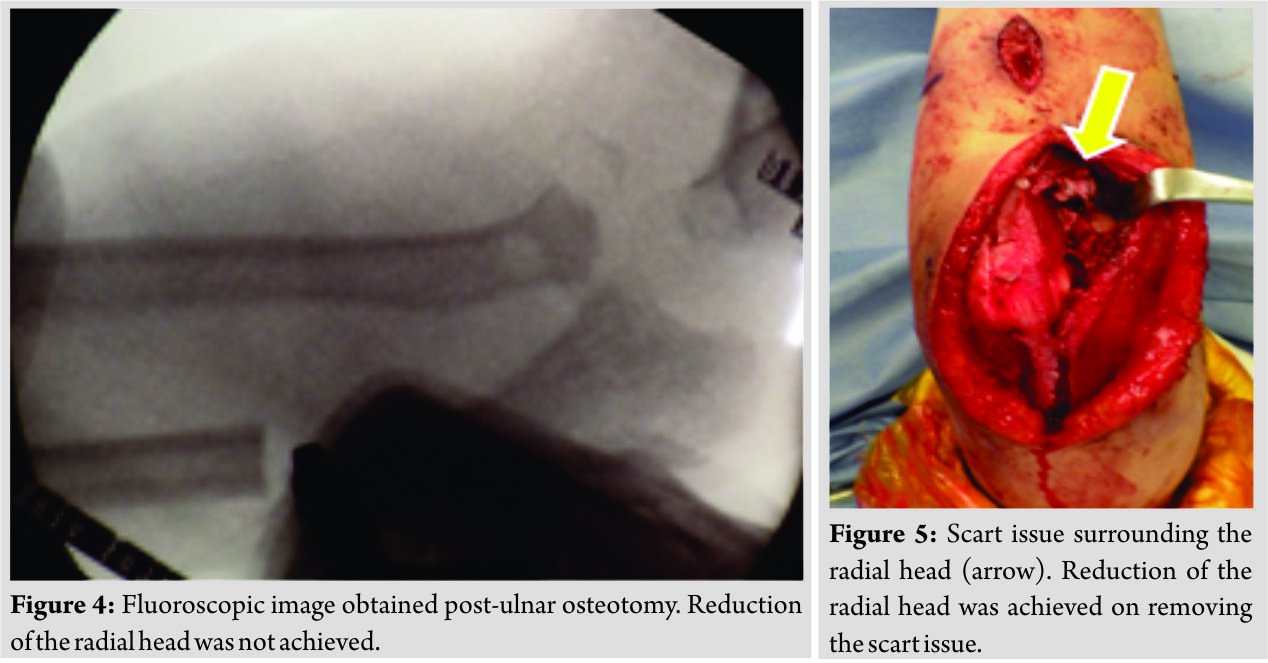

A 6-year-old girl was injured after falling off a kick scooter. A local physician diagnosed the injury as a left olecranon fracture, and she wore a splint for the following 3 weeks. Her plain X-ray revealed radial head dislocation and a proximal ulnar fracture (Fig. 1). A plain X-ray taken 1 month after injury revealed dislocation of the left radial head with surrounding calcification. The patient was referred to our department for examination due to persisting limited elbow range of motion. The patient exhibited considerably limited elbow range of motion at initial examination (flexion, 90°; extension, -25°; pronation, 90°; and supination, 0°) (Fig. 2). The plain X-ray also revealed anterior dislocation of the radial head with surrounding ossification as well as plastic deformation of the ulna (Fig. 3). Thus, a long-standing Monteggia fracture was diagnosed. The posterior elbow approach was used for surgery. Fasciotomy was performed using the Boyd approach, with an incision extending in a straight line from the olecranon to the triceps brachii muscle. Osteotomy of the proximal third-to-quarter of the ulna was performed, and the periosteum was preserved. Complete reduction could not be achieved using only ulnar osteotomy and straightening (Fig. 4).

The scar tissue and annular ligament remained intact, thereby hindering complete reduction (Fig. 5). The subluxation was reduced after surgically removing the scar tissue surrounding the radial head. The annular ligament was reconstructed using the Bell-Tawse method. Thereafter, 8 mm × 75 mm of the triceps muscle fascia was restored. To prevent obstruction of the triceps muscle fascia, two half-pins were inserted in the proximal and distal ulna, respectively. External fixation was performed using an Orthofix external fixator (M511). The correction angle was set at 20° (Fig. 6 and 7).